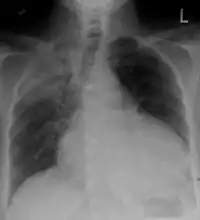

Chest x-ray: is non-specific and may not help identify a pericardial effusion but a very large, chronic effusion can present as "water-bottle sign" on an x-ray, which occurs when the cardiopericardial silhouette is enlarged and assumes the shape of a flask or water bottle.[2] Chest radiograph is also helpful in ruling out pneumothorax, pneumonia, and esophageal rupture.

A large anechoic (black) pericardial effusion as seen on ultrasound. Closed arrow: the heart, open arrow: the effusion Pericardial effusion due to malignancy. Note bulbous heart and primary lung cancer in right upper lobe.

Pericardial effusion due to malignancy. Note bulbous heart and primary lung cancer in right upper lobe. Pericardiocentesis: fluid aspiration of hemorrhagic effusion